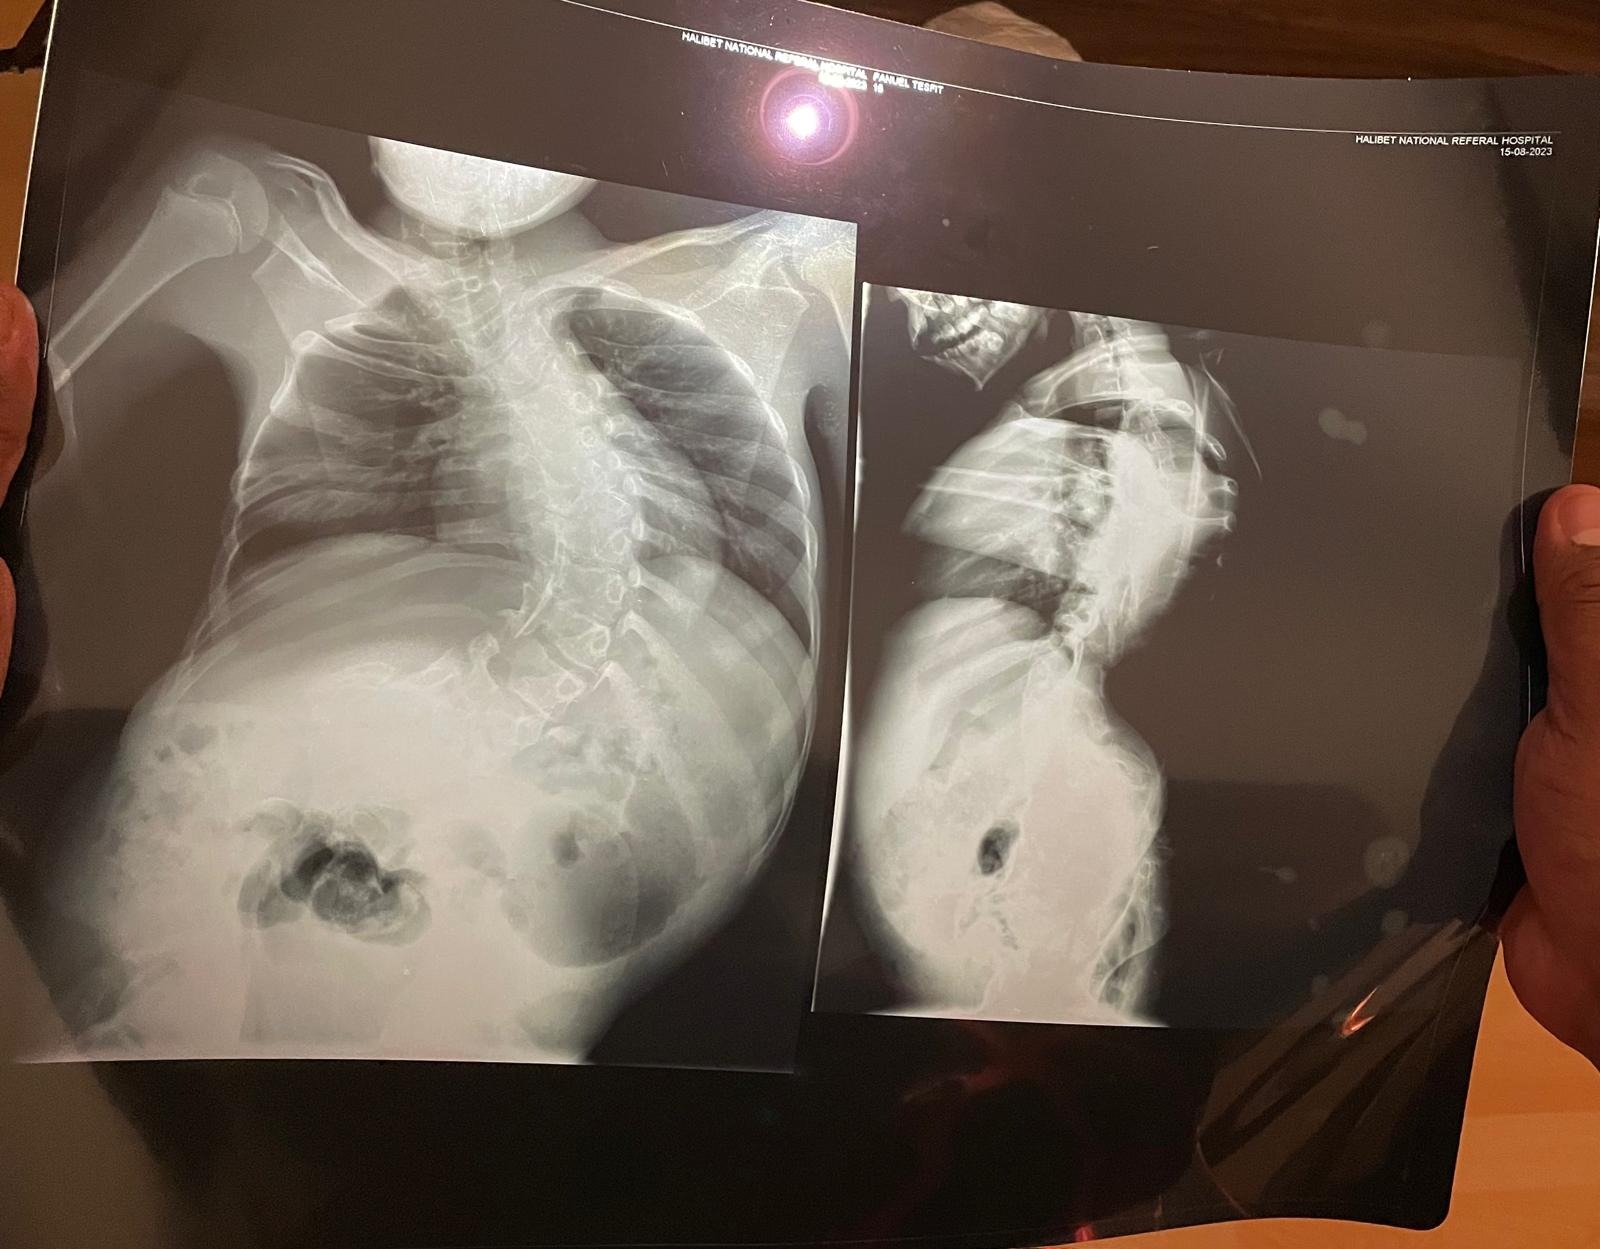

ወድና ፋኒኤል ተስፊት ኣብርሃም ተወላዲ ደቂ-ዳሽም (ንኡስ ዞባ ሎጐ ዓንሰባ) ካብ ህጻንነቱ ዝጀመሮ ናይ ዓንዲ ሕቆን ስርዓተ ሽንትን ሕማማት ንነዊሕ ኣብ ውሽጢ ሃገር ክሕከም ድሕሪ ምጽናሕ ንዝያዳ ሕክምና ናብ ኤሮፓ ክኸይድ ኣብ ሃገረ ኡጋንዳ ኣሎ ::

ወድና ግቡእ ሕክምና ክረክብን ከም መሳትኡ ክጐይን መጠን ገንዘብ ልዕሊ ዓቅምና ስለ ዝኰነ የሕዋት ሓገዝኩም ንሓትት::